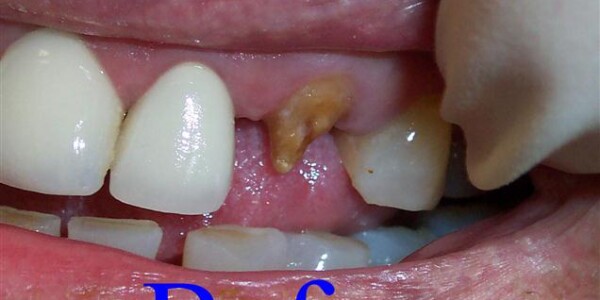

Restorative Dentistry

Restorative dentistry services focus on repairing teeth damaged to cavities, tooth decay, or trauma. From our beginning, it has been our goal to help our patients restore strength and structure to their smiles. We are committed to helping your smile stay beautiful and healthy for a lifetime. We incorporate the latest dental technology to ensure you receive the most advanced care. Our restorative services include:

Crowns